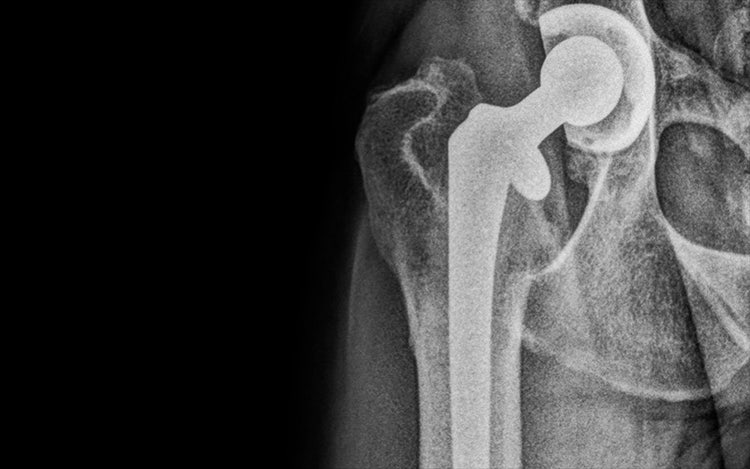

A German Shepherd has been given a new lease of life as a result of a Biomedtrix total hip replacement at Chestergates Veterinary Specialists.

The initial step in total hip replacement is thorough examination of each dog’s specific radiographic morphology and accurate digital templating. Most total hip replacement systems have a 5-10 % complication rate, but this figure can be minimised with meticulous planning. In this German Shepherd’s case, a cemented total hip replacement system was thought to be most appropriate, due her morphology and age. An innovative new Biomedtrix total hip replacement system, with a highly cross-linked polyethylene acetabular liner with the incorporation of Vitamin E, was used in this case. This change to the acetabular prosthesis is designed to increase the longevity of the acetabular cup. In total, the surgery time took two hours.

Post operation, the patient was advised to have six weeks of strict rest and recuperation to minimise the potential risk of potential complication, particularly dislocation. At the end of this period, she was clinically assessed by David and her follow-up radiography shows no complication.